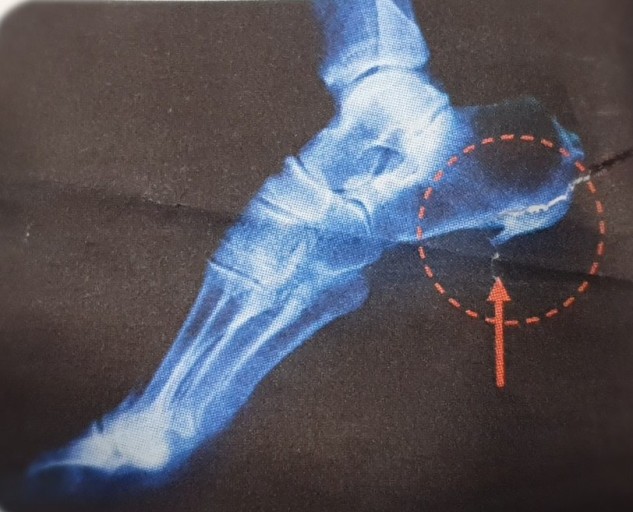

발바닥통증의 원인 고통성 족부 변형 (뼈 돌출 등)

- 발바닥의 뼈나 관절의 이상으로 인해 통증이 발생할 수 있습니다. 뼈의 돌출이나 과도한 뼈 성장(예: 발가락의 뼈가 튀어나오는 경우) 등이 그 예입니다. 이 경우 신발이 맞지 않거나 발에 가해지는 압력이 증가하여 통증이 유발됩니다.